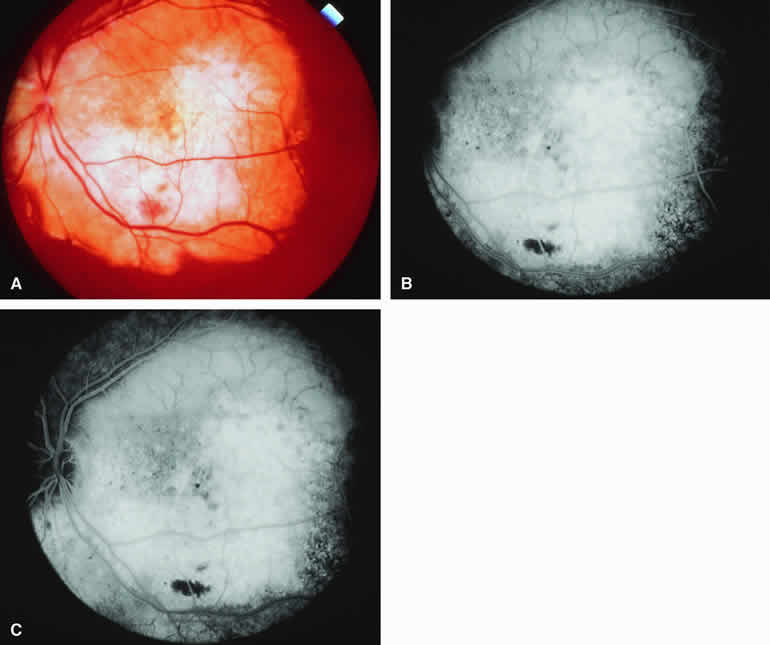

Fig. 16. Typical amelanotic metastatic carcinoma to choroid. A. Yellow-white choroidal tumor located interotemporal from optic disc. Note associated turbid subretinal fluid (most evident in maculopapillary bundle region). B-D. Fluorescein angiogram of lesion. B. Laminar venous phase frame showing ill-defined mottled hypofluorescence and hyperfluorescence corresponding to clinically visible lesion. C. Later laminar venous phase frame still showing no distinct choroidal mass. D. Late-phase frame showing diffuse hyperfluorescence corresponding to lesion and leakage of fluorescein into subretinal space.

Typical Amelanotic Choroidal Metastatic Tumor

On fluorescein angiography, the typical metastatic tumor (see Figs. 16B, C, and D and 17B, C, and D) appears relatively hypofluorescent in the early frames of the study but becomes progressively more fluorescent as the study continues. Few, if any, intralesional blood vessels are demonstrable. Because of the damaging effects of the expanding choroidal tumor on the overlying retinal pigment epithelium, diffuse or multifocal hypofluorescence and hyperfluorescence are often noted at the RPE level overlying the lesion. In addition, pinpoint hyperfluorescent foci at the RPE level, which are generally attributed to microcystic RPE degeneration, commonly become apparent over the surface of the tumor by the late frames. Fluorescein typically leaks through the retinal pigment epithelium to accumulate in the overlying and surrounding subretinal space by the late frames.